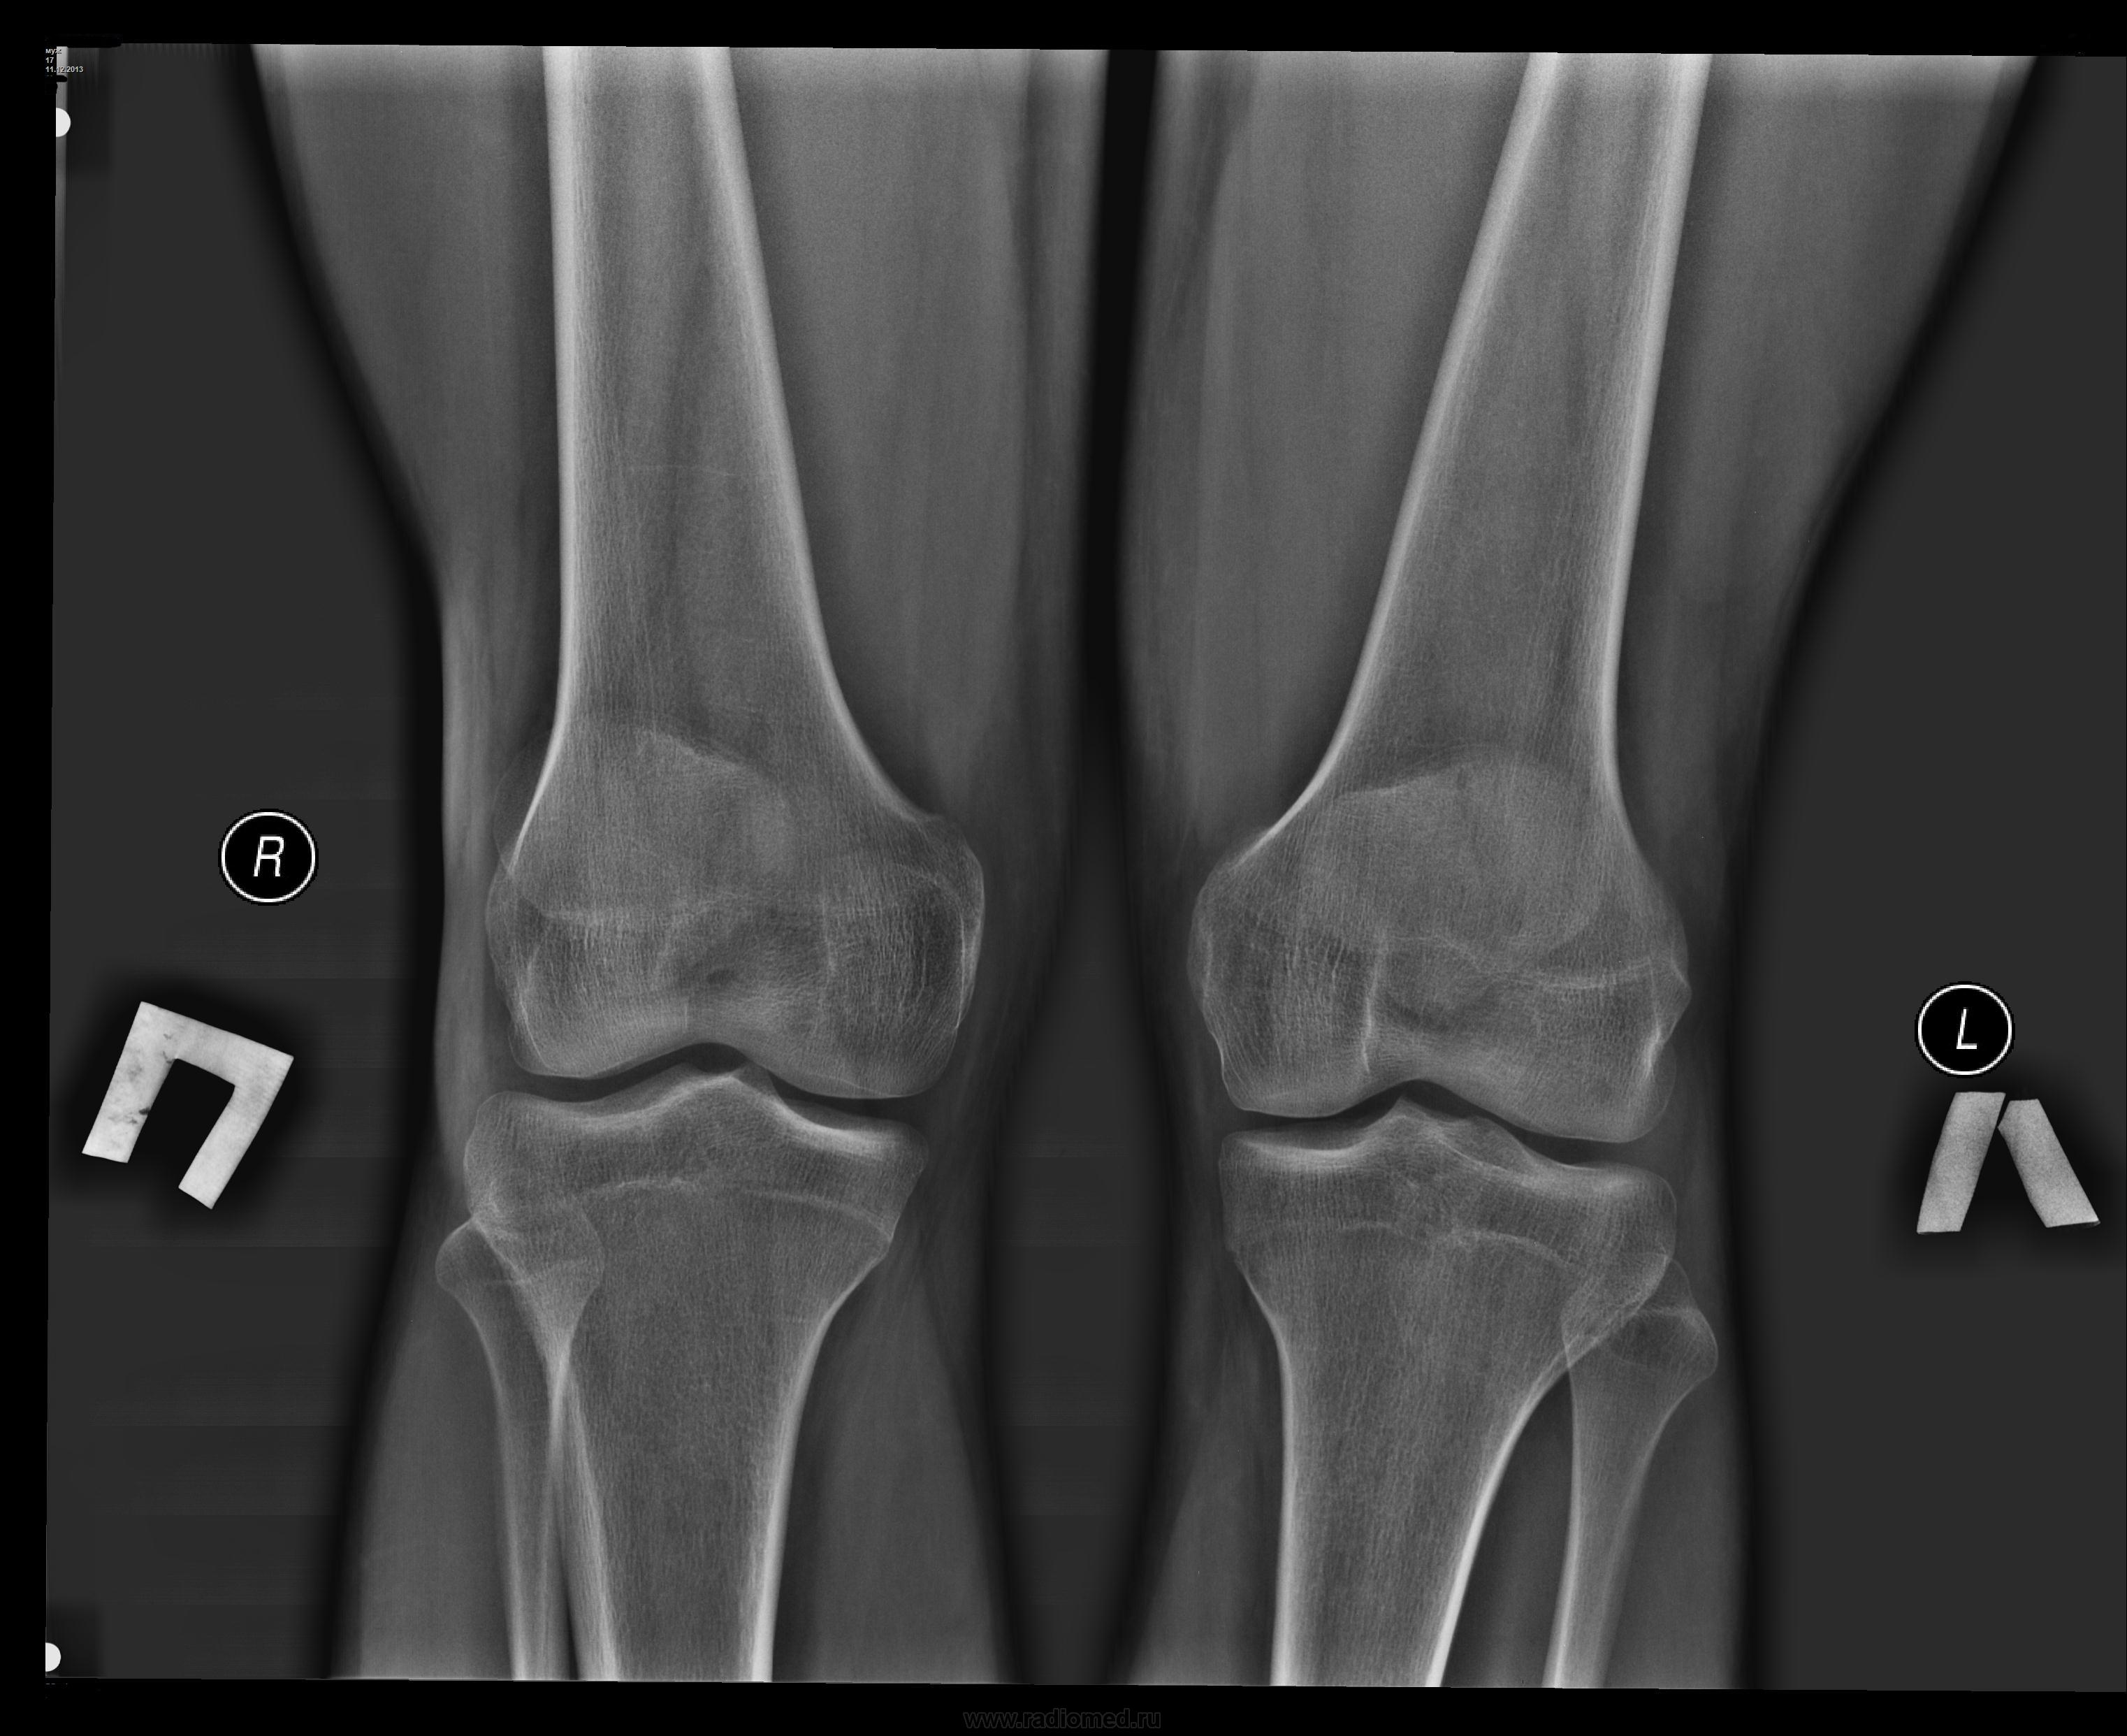

Парень, 17 лет, болезнееность при ходьбе в обоих суставах.

Костных изм. не видно.

По снимкам норма.

Артроза нет.

Рентгенологических данных за ДОА нет.